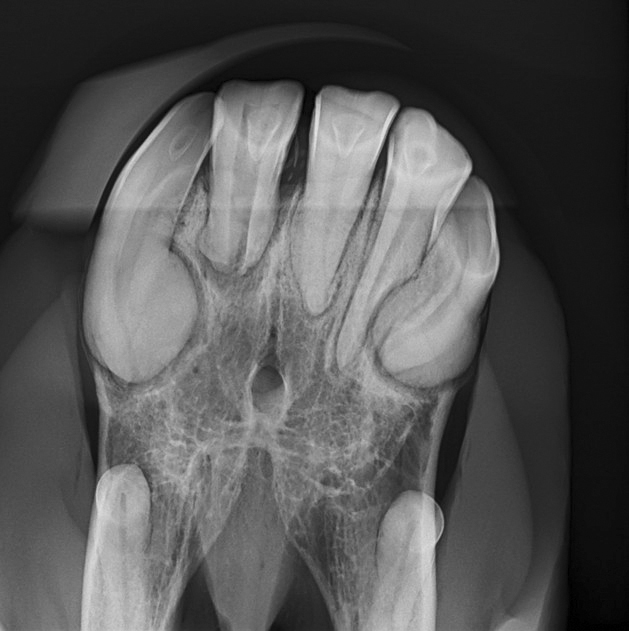

Äußerlich angewandt wird das flüssige Gold in der Wundversorgung sehr geschätzt.

Zur Behandlung oberflächlicher Wunden wird der Honig direkt auf den gesäuberten Bereich aufgetragen. Der hohe Zuckergehalt bewirkt die Bildung von reinigendem Wundsekret, indem er auf das darunterliegende Gewebe osmotischen Zug ausübt. Außerdem hält die dickflüssige Masse neue Bakterien vom Eindringen ab. „Die Feuchtigkeit ist auch bei Wunden von Vorteil, die durch einen Verband abgedeckt werden können“, erklärt Kerstin Hübner, „denn Honig sorgt für ein feuchtes Wundklima, was das Anhaften von Verbänden verhindert. Das ist für die Tiere angenehmer und beim Verbandswechsel reißt frisch gebildete Haut nicht wieder ab.“ Während der hohe Zuckergehalt die Wunde sauber und feucht hält, wirken weitere Inhaltsstoffe gegen Entzündungen und lassen das Wundareal abschwellen. „Gleichzeitig werden Schlackestoffe abtransportiert und die Heilung angekurbelt“, nennt die Therapeutin weitere Pluspunkte.

Pferde müssen oft im Stall unter nicht sterilen Bedingungen behandelt werden. Damit steigt das Infektionsrisiko. Hinzu kommt, dass eine Ruhigstellung an manchen Körperstellen, wie zum Beispiel dem Knie, schwierig ist, was die Wundheilung zusätzlich beeinträchtigt. Eine signifikante Beschleunigung der Heilung ist darum von erheblichem Vorteil. „Honig fördert das Wachstum von Fibroblasten, wodurch die Wunde gleichmäßiger heilt und es zu weniger Narbenbildung kommt“, sagt Dr. Gösmeier, gibt aber zu bedenken, dass bei alten Wunden mit Narbengewebe auch Manuka den Prozess nicht mehr rückgängig machen kann. Seine Stärke, so die Veterinärin, liegt in der Behandlung frischer Verletzungen sowie in der unterstützenden Pflege von Operationswunden. Auf frisch vernähte Wunden aufgetragen, unterstützt Manuka die rasche und nachhaltige Heilung.

Wunden heilen unter Honig schneller und problemloser ab, die Neubildung von Epithelzellen wird nicht gestört und nekrotisches Gewebe besser abgebaut. Die Tierärztin verwendet Honig gerne an Körperstellen, die keinen Wundverschluss zulassen oder nur langsam heilen und empfiehlt ihn auch als Must-Have in der Stallapotheke.